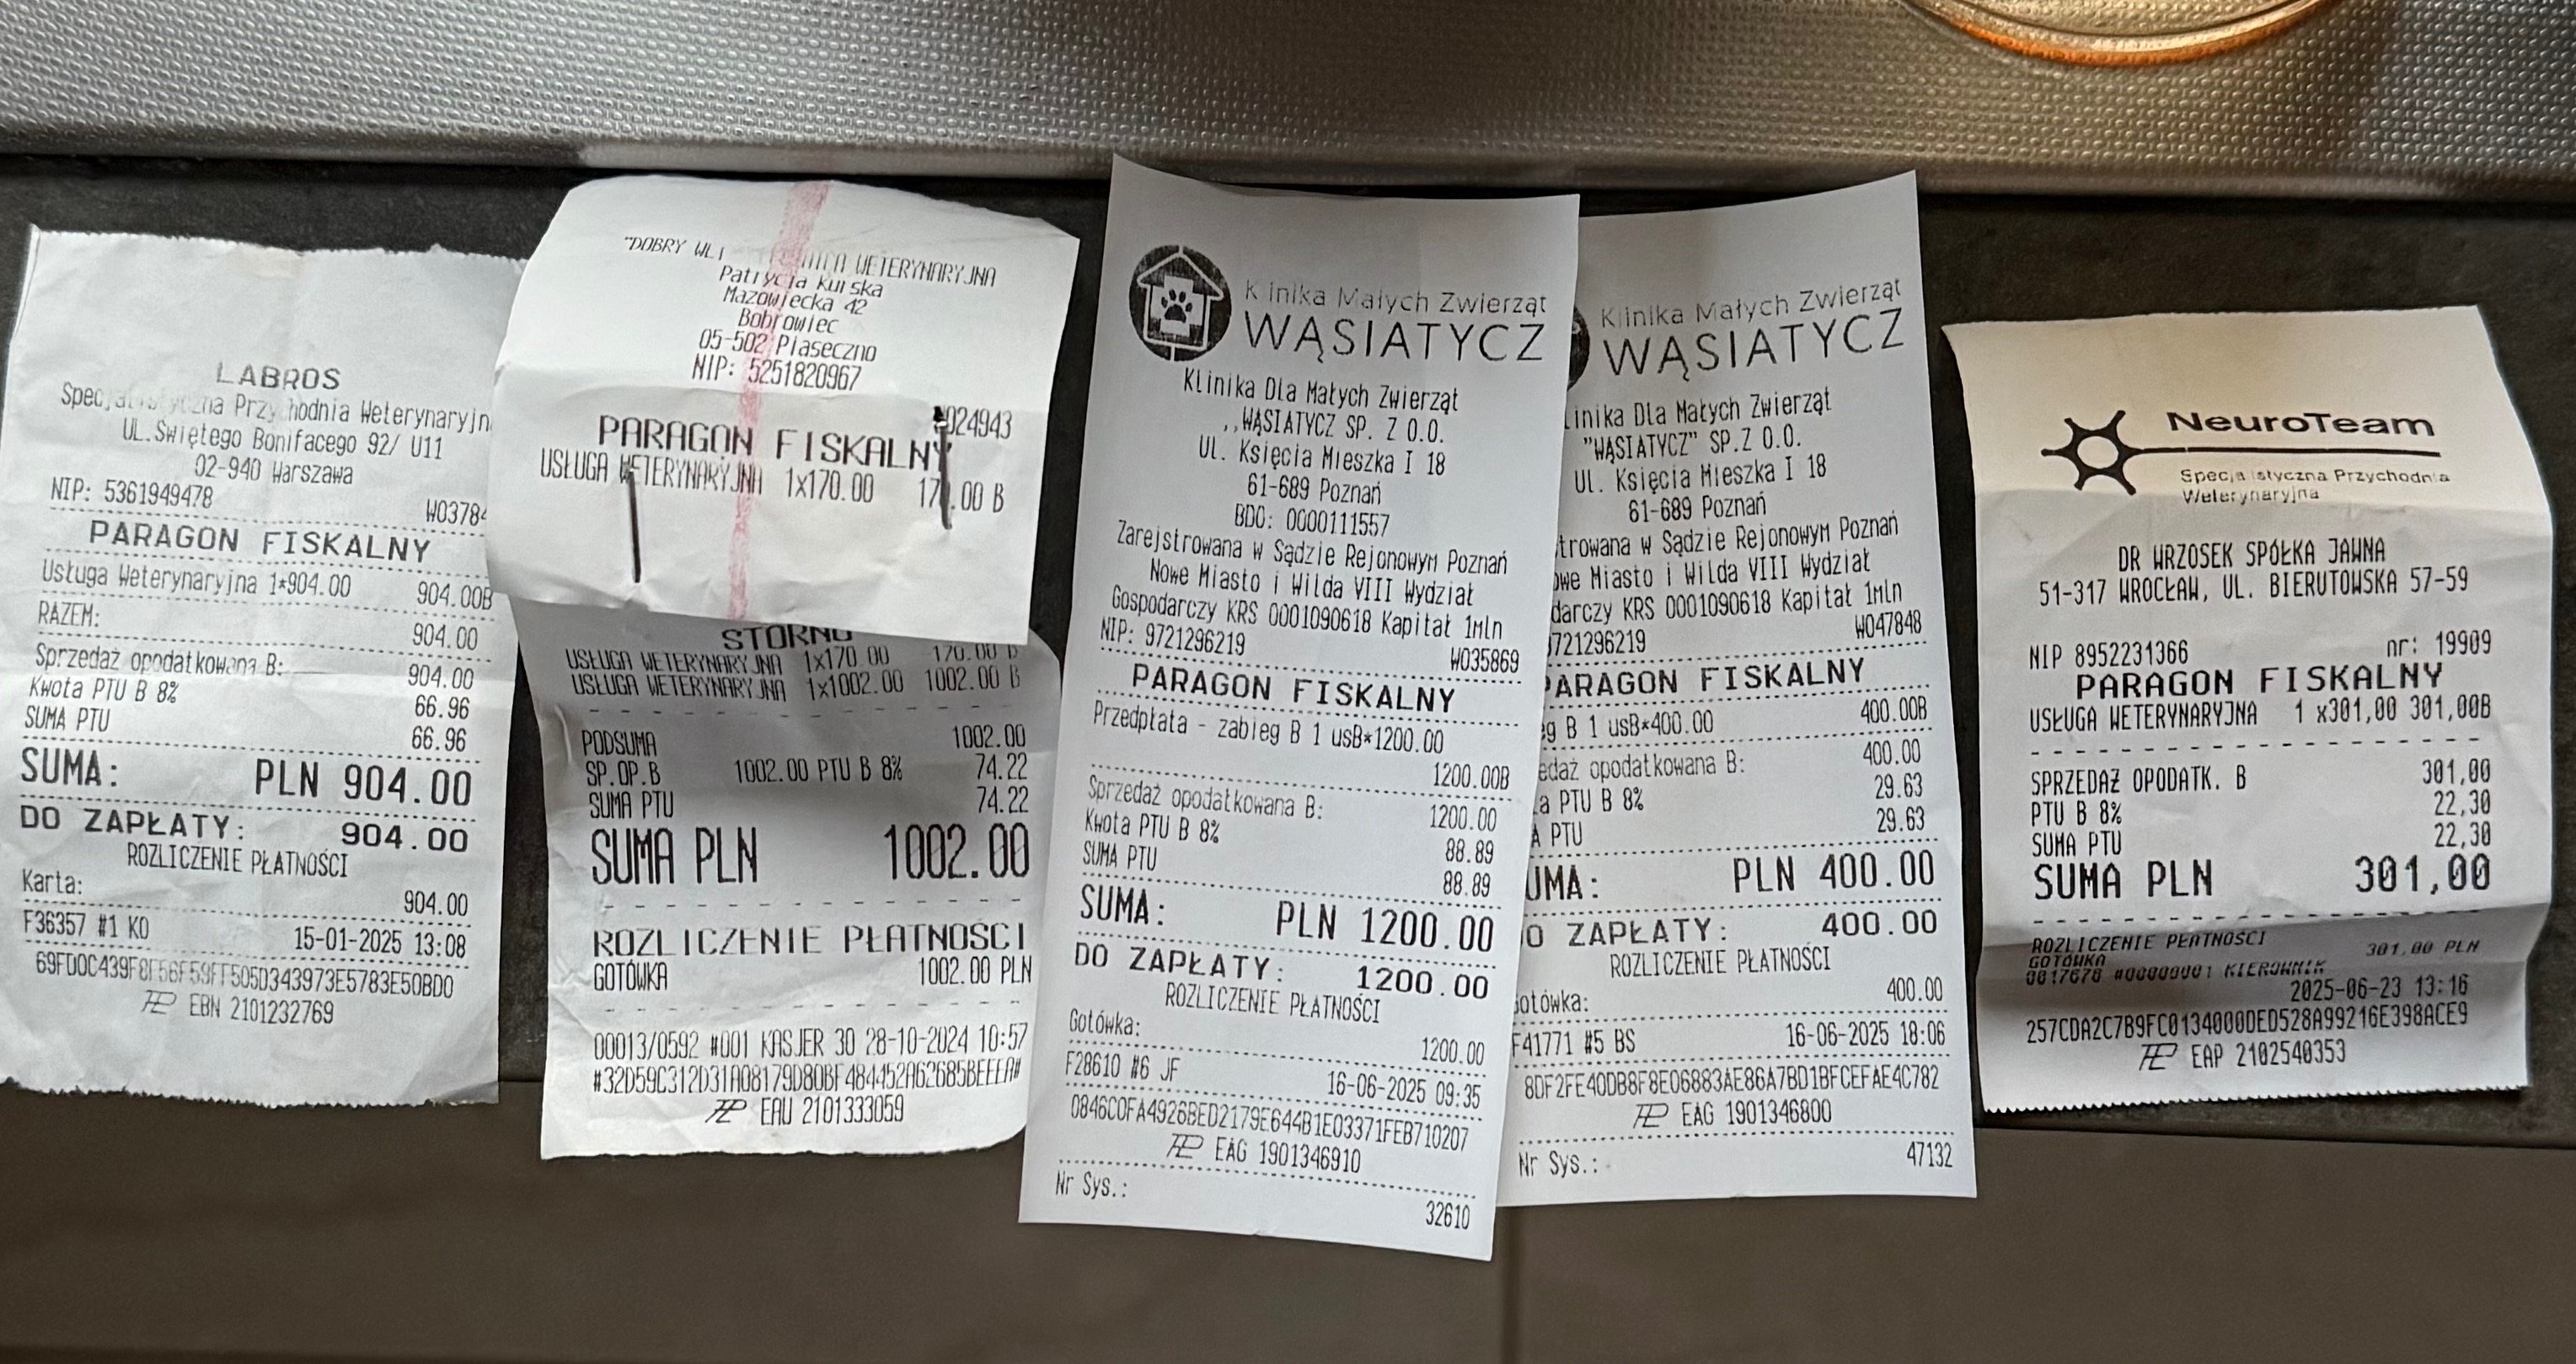

Cześć nazywam się Kinga Sucharska, jestem właścicielką już teraz 2 cudnych kotów. W styczniu 2025 pożegnałam swoją najstarszą kotkę, która zachorowała na nowotwór płaskonabłonkowy żuchwy. Dzisiaj zwracam się do Was z ogromną prośbą w imieniu mojego kotka 7 letniego Filusia o wsparcie finansowe i pomoc w jak najszybszym powrocie do normalnego funkcjonowania i szansy na dalsze życie. Po prawie 2 latach diagnostyki, leczenia w ciemno, czy doraźnej pomocy farmakologicznej otrzymaliśmy diagnozę w postaci nowotworu mózgu jakim jest OPONIAK. Na szczęście dostaliśmy szansę i możliwość na usunięcie guza w klinice NeuroTeam we Wrocławiu. Niestety Koszt takiej operacji wynosi od 15 do 18 tysięcy złotych. Pomijając koszty dalszego leczenia, dojazdów czy ewentualnej dalszej hospitalizacji kotka (cena za dobę w klinice to koszt 900zł). Niestety koszta tejże operacji przerastają Nas, tym bardziej, że jego wcześniejsze diagnozowanie wyniosło mnie już ogromną sumę.

Załączam jedne ze świeższych paragonów, które udało mi się znaleźć. Jest to kropla w morzu…